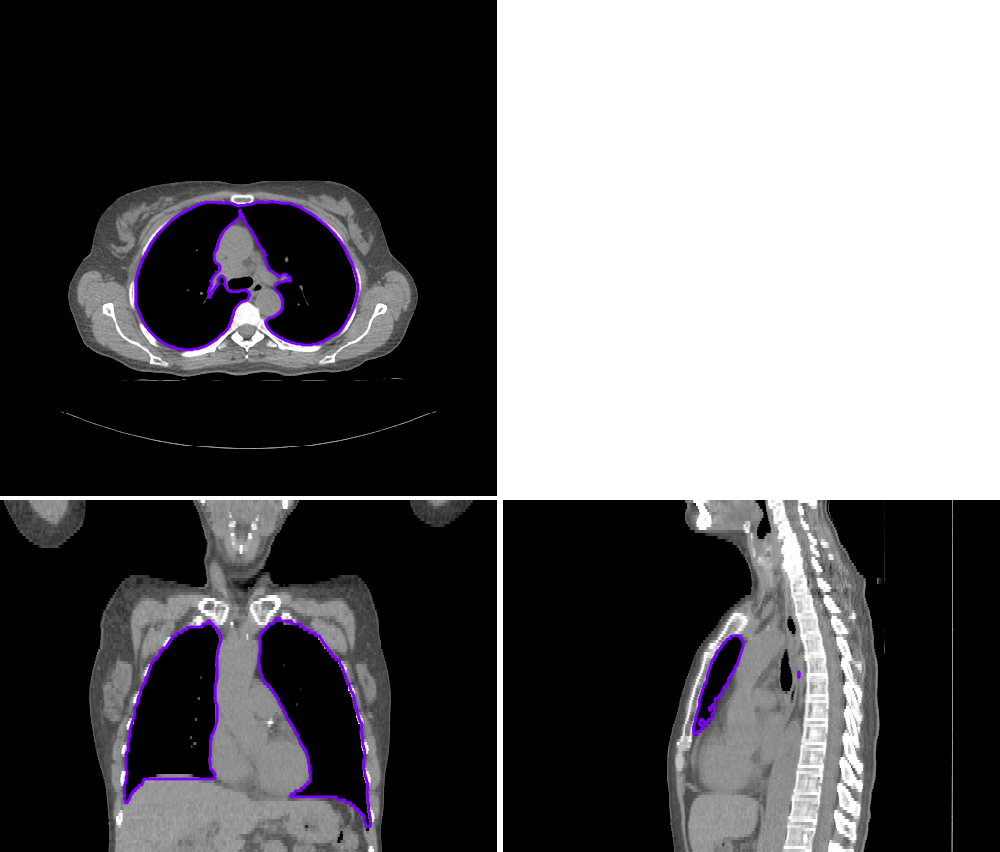

我试图绘制一个图像的轮廓,并使它覆盖到原来的图像,但没有填充,我希望它显示为一个边缘轮廓,而不是一个填充的轮廓,如附图。

我使用了这个命令,但问题是当我使用LabelOverlay函数时,图像对比度发生了变化!虽然我需要保持相同的图像强度,有什么办法解决它吗?代码是: sitk_show(SimpleITK.LabelOverlay(imgOriginal1,SimpleITK.LabelContour(ImgOriginal2))

下面是一个示例:

import SimpleITK as sitk

from platipy.imaging import ImageVisualiser

img = sitk.ReadImage("./CT.nii.gz")

mask = sitk.ReadImage("./MASK_LUNGS.nii.gz")

vis = ImageVisualiser(img)

vis.add_contour(mask)

fig = vis.show()

fig.savefig("example.jpeg", dpi=300)

这个工具是高度定制的,请查看关于Github :-)的文档。)